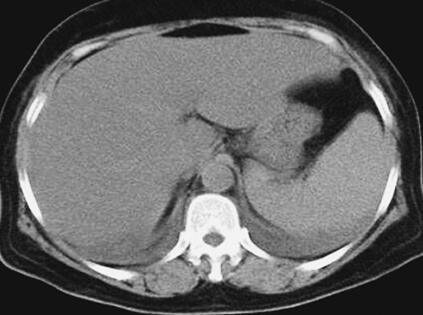

患者,女性,59岁。因“发热8天,上腹部隐痛、腹泻伴胸闷7天”于2011年7月8日入院。患者8天前出现发热,39.5℃,无畏寒、寒战,在当地卫生院予输液治疗(具体不详),症状未好转。7天前出现上腹部隐痛、腹泻,日约4~5次,黄色稀便,伴胸闷,遂就诊于当地镇医院,心电图检查正常,拟“中暑”,予针灸等治疗后无好转。2天前就诊于当地县人民医院,查血常规:WBC 8.4×109/L,N 89.2%,Hb 102g/L,PLT 92×109/L;肥达反应阴性;肝功能:ALT 104IU/L,AST 144IU/L,TP 55g/L,ALB 27g/L;腹部CT:脂肪肝,脾肿大;胸部CT:两肺少许炎症,左侧可疑少许胸腔积液,拟败血症,中毒性肝炎,伤寒住院治疗;期间体温波动于38~39℃,血压波动于80/50~90/60mmHg,予多巴胺[6.0μg/(kg·min)]升压,予亚胺培南-西司他汀钠联合头孢曲松抗感染治疗,病情无好转,仍有发热、腹泻、上腹部隐痛不适,并出现尿量减少、血肌酐升高。于7月8日转笔者医院急诊,测血压[多巴胺6.0μg/(kg·min)维持]89/55mmHg,血常规:WBC 10.28×109/L,N 89.4%;Lac 2.3mmol/L,CRP>90.0mg/L,Cr 141μmol/L,cTnI 6.02μg/L,BNP 577pg/ml;胸腹部CT:两下肺背侧散在炎症,两侧胸腔少量积液,慢肝样病变,胆囊结石(图1、图2);腹部B超:脂肪肝,脾偏大,拟发热待查,心肌炎?感染性休克?,予补液、亚胺培南-西司他汀钠控制感染,多巴胺升血压,为进一步治疗拟上述诊断收入急诊重症监护病房。既往史:40年前发现胆囊结石。

图1 胸腹部CT:两肺纹理增多增粗,两下肺背侧见斑片高密度影,边界模糊;两侧少量胸腔积液(7月8日)

关于恙虫病的肺部改变报道较多。有59%~72%的恙虫病患者可有肺部表现,胸部CT表现可以有磨玻璃影、纵隔淋巴结肿大、小叶间隔增厚、胸腔积液、肺门淋巴结肿大,间质增厚、实变,小叶中心性结节。恙虫病可伴有急性呼吸窘迫综合征(ARDS),是一种少见但很严重的并发症。年龄大、血小板减少、早期肺炎(出现呼吸窘迫前2天,胸片上出现浸润征象)均是ARDS的诱发因素。该患者表现为呼吸促,胸部CT表现为双肺纹理增多、增粗,两下肺背侧见斑片样高密度影,边界模糊;两侧少量胸腔积液,氧合指数<200,考虑并发ARDS。